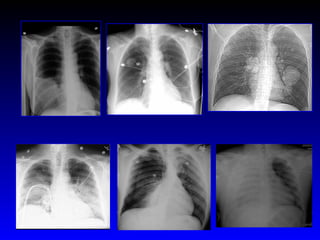

INTERESTING  CASES INFECTION NEOPLASTIC CARDIOVASCULAR TRAUMA

Empyema after trauma Clavicle fracture Cavitary lesion Opacified hemithorax